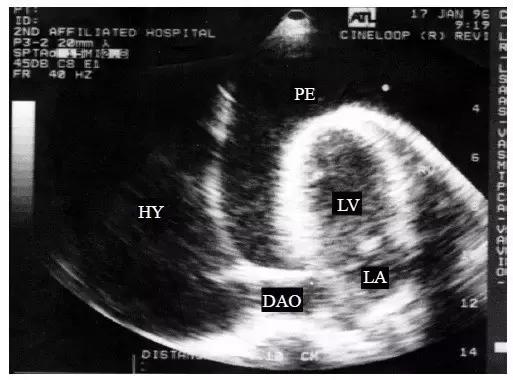

【大量心包积液】

1.整个心脏被无回声区所包绕,心尖及左心室后壁心包腔内暗区最宽(图3)。

图3 大量心包积液的二维超声心动图表现

整个心脏被无回声区所包绕,心尖及左心室后壁心包腔内暗区最宽

2.大量积液无心包粘连时,悬吊在大血管下的心脏可在液体内自由摆动,称“摆动征”,即收缩后期向前运动,舒张期向后运动,摆动的幅度与液体的黏稠度密切相关。右心室前壁活动幅度增强,呈波浪式运动,左心室后壁幅度降低。